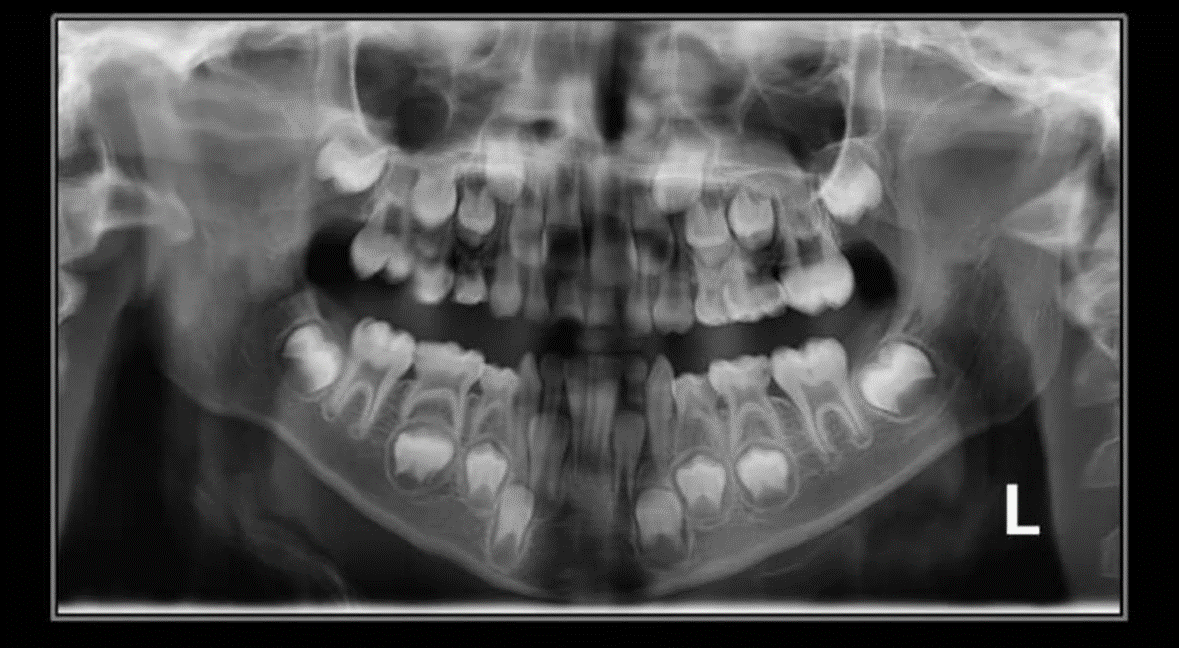

1. How old is the patient with the following X ray?